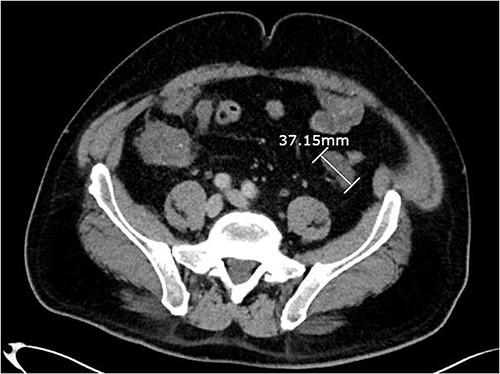

About 1 year later, the patient re-presented for anaemia and underwent a further CT scan. In the right iliac fossa, a 51.96 mm mass was noted such that the appendix could not be visualized separately, with a focus of calcification (Fig. 1). There was infiltration into the adjacent fat and abnormal soft tissue thickening of the peritoneal reflection along the right paracolic gutter. Multiple new peritoneal nodules in the upper abdomen were also identified (Fig. 2). The appearances were in keeping with disseminated malignancy. Following histological analysis, diagnoses of LAMN and PMP was made. The patient was initiated on mitomycin and capecitabine chemotherapy, which modestly reduced the size of the right iliac fossa mass from 51.96 mm to 44.23 mm (Fig. 3).

Axial CT abdomen with contrast demonstrating a peritoneal deposit posterior to the descending colon in the left iliac fossa, measuring 37.15 mm.